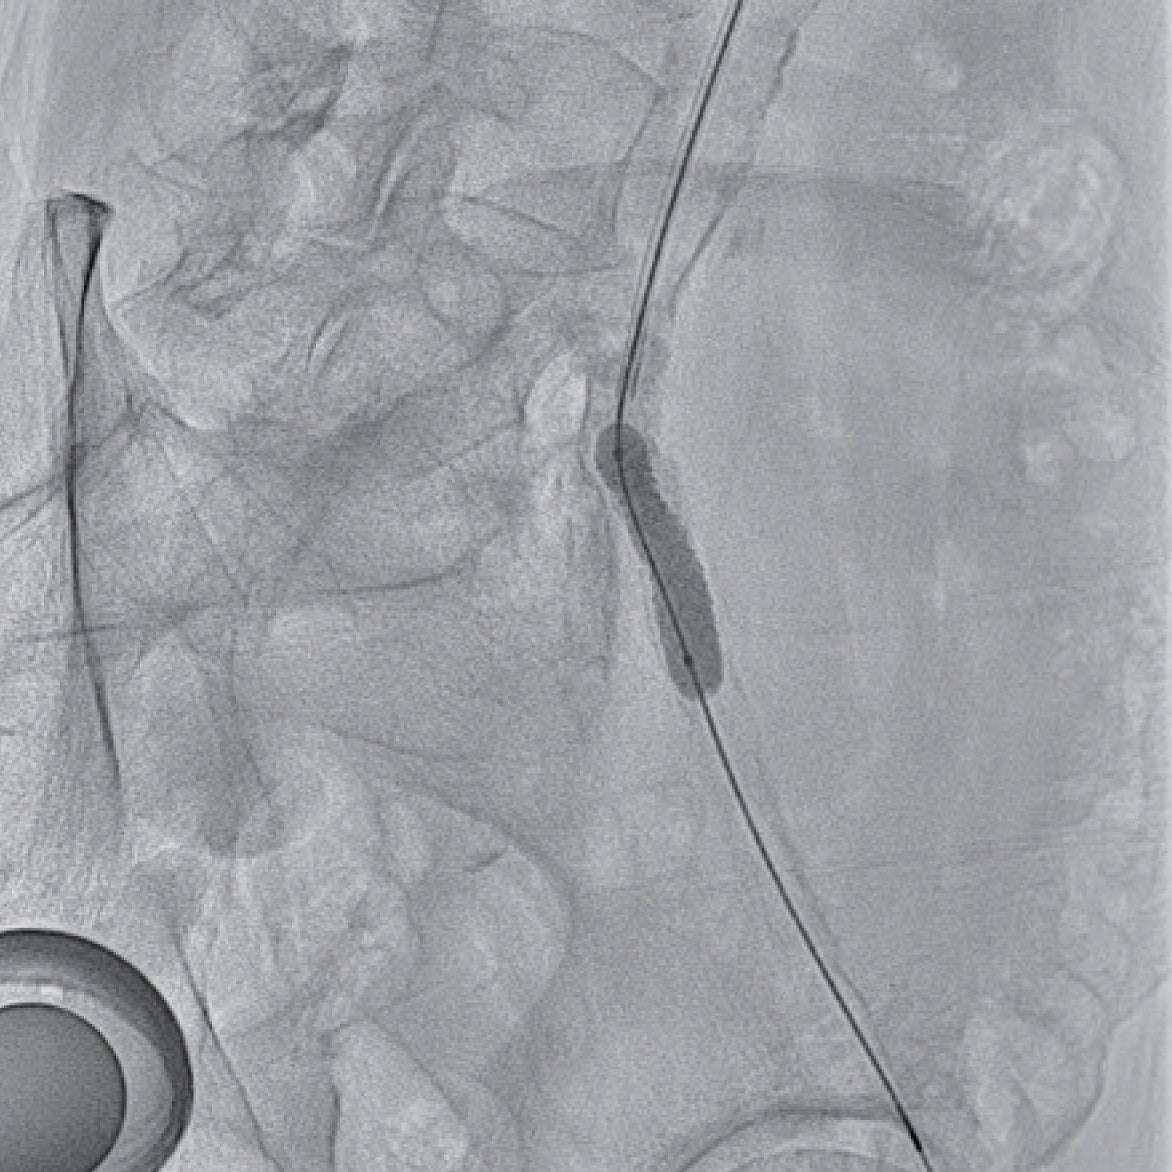

6 Frガイディングシースに変更しガイディングシースを左総腸骨動脈まで進めた。ガイドワイヤー通過は困難であったが、何とか0.014 inchガイドワイヤーを通過させて(図1b)、小径のバルーンで拡張後、IVUSで病変を評価した(図2)。全周性の表在型石灰化病変であり、通常のベアメタルステントでは拡張できないことが想定され、また内腸骨動脈との分岐部直下に置けるため、ステントグラフトの適応と判断した。6.0 × 40 mmのバルーンで拡張後、6 Frシステム対応のVBX ステントグラフト7.0 × 39 mmを留置、8.0 × 40 mmのバルーンで後拡張を実施(図3)した。IVUSで十分な血管内腔の確保を確認し(図4)、最終造影を行い、治療を終了した。穿刺からシース抜去までの手技時間は38分で、患者は車椅子で退室し、ベッド上の安静時間はゼロであった。足関節上腕血圧比(ABI)は術前の0.70から1.02まで上昇した。

図2

図4